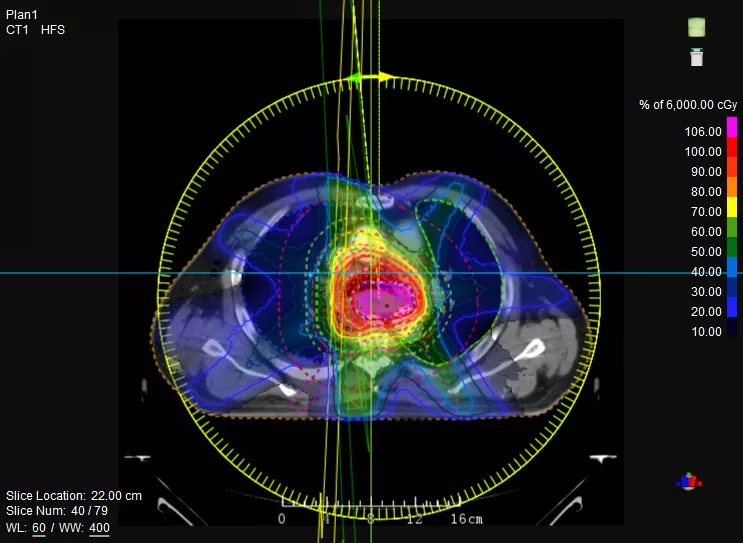

一款設備即可滿足CT模擬定位、CT影像引導、uARC動態(tài)旋轉調(diào)強放療等重要臨床應用,無需科室/治療室間切換,一站完成放療全流程。

機載CT影像可直接用于放療計劃制作

CT-IGRT配準,除骨性標記外,還能以器官、軟組織等作為參考,真正找到配準目標

鼻咽癌患者,進行旋轉容積調(diào)強治療(uARC)